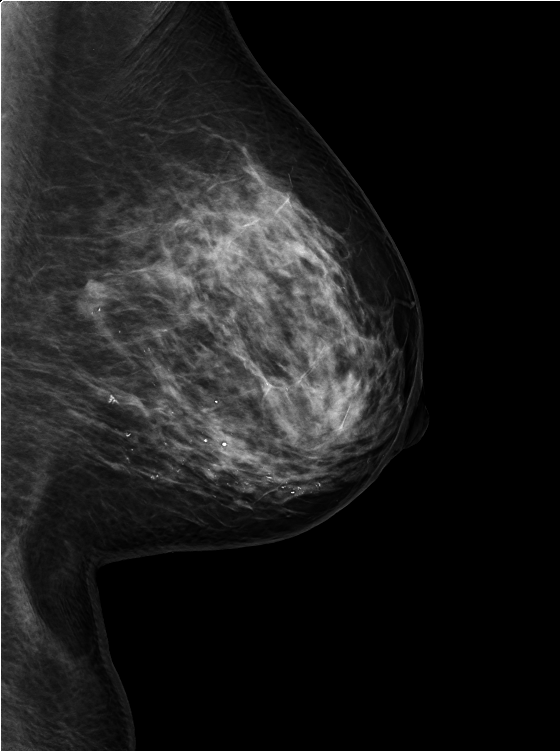

当院では最新の 3Dマンモグラフィ(トモシンセシス) を導入しており、従来のマンモグラフィ画像(2D)に比べて乳腺の重なりを分離して表示できるため、小さな病変や見えにくい部分も評価しやすくなります。(左が3D, 右が2D)

マンモグラフィの2Dと3D(トモシンセシス)について

2Dマンモグラフィ

従来法。一般的なマンモグラフィ検査のことです。1回の圧迫で平面画像を得ます。石灰化の評価にすぐれます。

3Dマンモグラフィ(トモシンセシス)

薄い断層画像を重ねて立体的な画像を作る方法です。乳腺の重なりによる見えづらさが低減されるので、小さな病変や腫瘤も発見しやすいです。2Dと比べて精度が高いので、見落としや再検査を低減できるメリットがあります。

2Dマンモグラフィと3Dマンモグラフィの比較

項目 2Dマンモグラフィ 3Dマンモグラフィ(トモシンセシス)

撮影方法 乳房を圧迫して2方向(上下・斜め)から平面画像を撮影 乳房を圧迫し、X線の管球が移動して乳房を多方向から複数枚撮影→断層画像を再構成(3D)

画像の特徴 平面的な1枚画像で、乳腺や病変が重なって写ることがある 1mmごとのスライス画像で乳腺重なりを分離し、立体的に観察できる

検出精度 高濃度乳腺では病変が隠れることがある 高濃度乳腺でも腫瘤・石灰化をより明瞭に描出できる